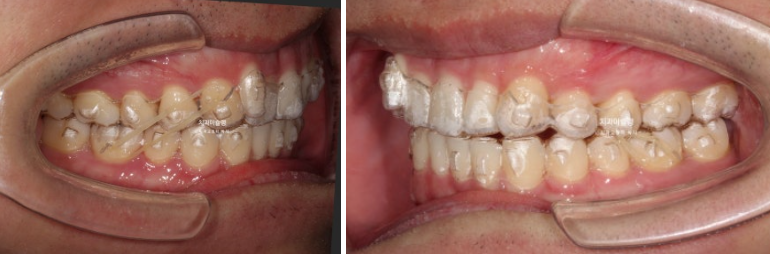

또한 측모에서 보면 위 앞니가 옥니입니다.

즉 치아가 뒤로 쓰러져 있습니다.

어금니 교합관계는 2급입니다.

위에 사랑니를 빼고 사랑니 공간으로 위 어금니들을 뒤로 밀어내야 1급 교합관계 달성이 가능합니다.

24.03~25.11

아래 앞니 블랙트라이앵글은 치축의 개선과 소량의 치간삭제로 사이즈를 줄였습니다.

어금니 교합은 기존 2급에서 1급 교합관계를 달성